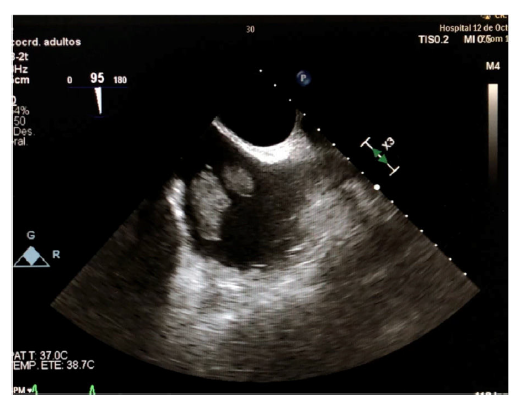

Varón de 70 años de edad, quien acudió a urgencias por episodio vasovagal con hallazgo incidental de fibrilación auricular con respuesta ventricular controlada, que se trató de manera ambulatoria mediante anticoagulación oral con acenocumarol. Durante el control ambulatorio, dos meses después, se hizo ecocardiograma transtorácico en el que se evidenció masa auricular derecha de gran tamaño (fig. 1), motivo por el cual fue ingresado. Se completó el estudio con un ecocardiograma transesofágico que reportó dos masas contiguas (32x18mm y 16x22mm) en la desembocadura de la vena cava inferior, dependientes de la válvula de Eustaquio, que atravesaban la aurícula derecha y alcanzaban el septo interauricular sin comprometer la función de la válvula tricúspide (figs. 2 y fig 3). Como primera posibilidad diagnóstica se planteó un mixoma auricular y ante la posibilidad de embolización se optó por manejo quirúrgico, no sin antes efectuar una coronariografía, que no reportó lesiones; se programó para resección del mixoma. Durante la cirugía se hallaron dos masas de aspecto fibroelástico (fig. 4 ) que no se relacionaban con el septo y que al ser resecadas no alteraban la competencia de la válvula tricúspide. La cirugía y el postoperatorio cursaron sin complicaciones y el estudio anatomo-patológico informó que las masas correspondían a trombos, sin hallazgos de componente tumoral. Durante el seguimiento a seis meses permanecía asintomático y en ritmo de fibrilación auricular.

Figura 2 Ecocardiograma transesofágico en una proyección en la que se observan las cavas y se evidencian dos masas en la desembocadura de la vena cava inferior, dependientes de la válvula de Eustaquio.